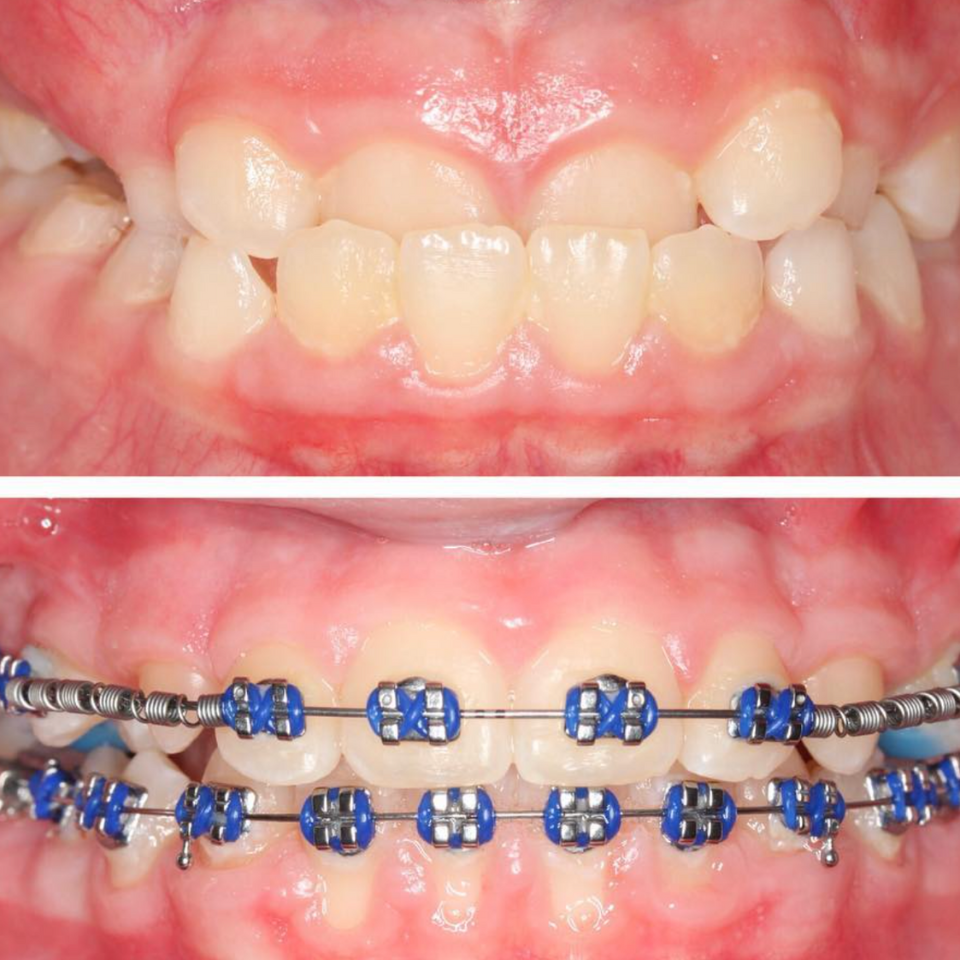

BEFORE AND AFTER PHOTOS

Align Orthodontics smile transformations focus on subtle, strategic adjustments—delivering natural-looking results that enhance facial harmony and overall balance.